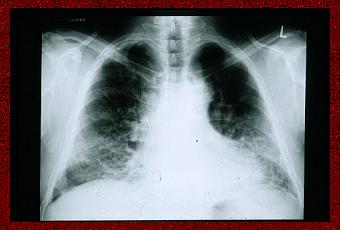

Radiographie du poumon d'un patient atteint de fibrose pulmonaire idiopathique. On observe la petite taille des poumons et l'opacification réticulo-nodulaire périphérique.